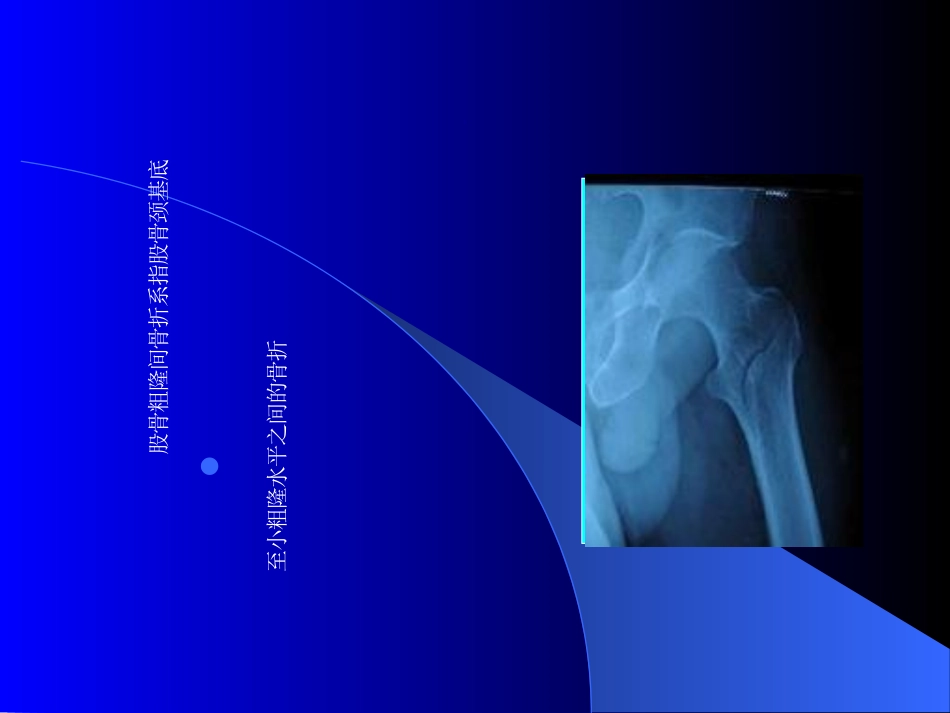

股骨粗隆间骨折股骨粗隆间骨折定义股骨粗隆间骨折系指股骨颈基底至小粗隆水平之间的骨折股骨近端解剖图诊断依据1、病史:外伤史2、查体:移位型骨折患肢呈外旋、短缩、内收畸形;大粗隆处压痛、纵轴叩击痛阳性,有的可扪及骨擦音或骨擦感;患髋活动障碍;3、X线摄片可明确诊断和骨折的类型分型ØEvans分型(1949)ØEvans-Jensen分型(1975)ØAO分型(1981)分型Evans分型分型Evans-Jensen分型骨折特点1、多见于老年人,长期卧床带来的并发症是老年人死亡的主要原因,西方又被称为成人最后一次骨折;2、属于关节囊外骨折,很少发生骨折不愈合或股骨头缺血性坏死,但保守治疗易出现髓内翻,形成畸形连接,承重力线的改变,导致破行、创伤性关节炎。治疗文献资料证明,保守治疗比手术治疗有较高的致残率和致死率。近年来随着高龄患者围手术期管理水平的提高及内固定器材的改进,此类骨折倾向于手术治疗。手术固定治疗的方法分为:髓外固定、髓内固定髓外固定动力髋螺钉(DHS:Dynamichipscrew)动力髁螺钉(DCS:Dynamiccondylescrew)经皮加压钢板螺钉(PCCP:percutaneouscompressionplating)解剖型锁定钢板倒打LISS钢板髓内固定GammaNail、PFN、PFNA、TFN内固定器械Ø更坚强稳定的固定,以利于早期负重功能锻炼Ø更低的股骨头切割、内固定物松动和其它并发症Ø更简易的植入技术Ø加压技术,促进骨折更快愈合Ø可微创操作,以减少手术期间并发症Ø费用低廉尖顶距Ø1995年Baumgaertner提出Ø正侧位X片上拉力螺钉尖至股骨头-颈中轴线与股骨头关节面交点的距离之和Ø小于25mm或20mmØ评价拉力螺钉的位置,预测螺钉切出风险尖顶距DHSØ理解DHS的器械特点,能滑动加压Ø选择骨折类型,稳定骨折并发症较少Ø因为主钉能滑动,故外侧壁要完整Ø张力侧髓外固定,要求内侧压力侧有支撑Ø微创置入保护血供能提供更好的骨愈合DHSDCSØ可视为重建了外侧壁Ø原设计为固定股骨髁的内植入物活用于股骨粗隆间骨折Ø相对于其他内固定物优点不多,临床文献报道较少DCSØ头颈内两颗螺钉,稳定性好,滑动位移更小Ø微创植入方法,出血少、创伤小Ø手术时间短Ø放射投照时间减少Ø术后失败率及再手术率减少Ø具有DHS其它的优点PCCPPCCP倒打LISSØ骨质疏松,不稳定骨折,粉碎性骨折较适用Ø利用桥接及微创技术Ø原来设计为固定股骨远端的桥接钢板,是不是也受DCS启发用于股骨粗隆间骨折?倒打LISSNoImageTHANKYOUSUCCESS24/10/2026可编辑解剖锁定板GammaNailPFNØ复杂的粉碎的骨折Ø不稳定的骨折Ø反斜骨折Ø粗隆下骨折PFNPFNAØ对于不稳定的粗隆间骨折是一种理想的内植物Ø可牢固地固定股骨头和股骨颈,防止骨折端旋转Ø防止内侧支撑缺失后骨吸收导致的塌陷、内翻畸形及内植物切出股骨头等并发症Ø适用于几乎所有的粗隆间骨折,特别适用于不稳定型骨折及合并骨质疏松Ø仍有一定的并发症,如股骨头穿出操作要点Ø手术入路Ø进针点正位位于大转子顶点侧位位于大转子前1/3Ø进针方向正位应适当向内偏斜侧位应稍向前主钉Ø主钉设计与髓腔解剖形态达到最佳匹配Ø主钉6°外展角,便于从大转子顶点置入Ø空心主钉,置入方便Ø主钉远端有一定的弹性,易于主钉插入螺旋刀片Ø抗旋转和成角稳定Ø增强锚合力Ø提高抗切出能力Ø股骨颈中央略偏下Ø长度合适远端锁钉Ø静态和动态锁定PFNAPFNAPFNATFNØ螺旋刀片尾部是斜行的Ø螺旋刀片是一个整体关节置换Ø有助于患者术后迅速恢复功能Ø减少力学风险和内固定物相关风险关节置换治疗策略Ø骨骼质量Ø骨折类型Ø骨折复位程度Ø内植物设计选择Ø内植物的安放位置内固定失败Ø内固定选择不当Ø内固定植入位置不当Ø复位较差Ø负重过早Ø骨质疏松失败病例失败病例失败病例粗隆下骨折,DHS术后断裂,更换为解剖钢板,再次断裂。失败病例对于稳定性骨折选择髓还是髓外固定关键是决定于手术医生的习惯或者说对内固定的掌握的熟练程度。非稳定性骨折更主张选择髓内固定,能闭合复位一定不切开复位骨质疏松明显的老龄骨折选择螺旋刀片钉(PFNA).个人观点围手术期并发症Ø感染Ø下肢深静脉血栓Ø精神错乱Ø脏器功能不全小结Ø熟悉骨折分类及意义Ø全面掌握病人的全身情况Ø了解所使用器械的作用机制及适应症Ø掌握一定手术技巧NoImageTHANKYOUSUCCESS24/10/2051可编辑